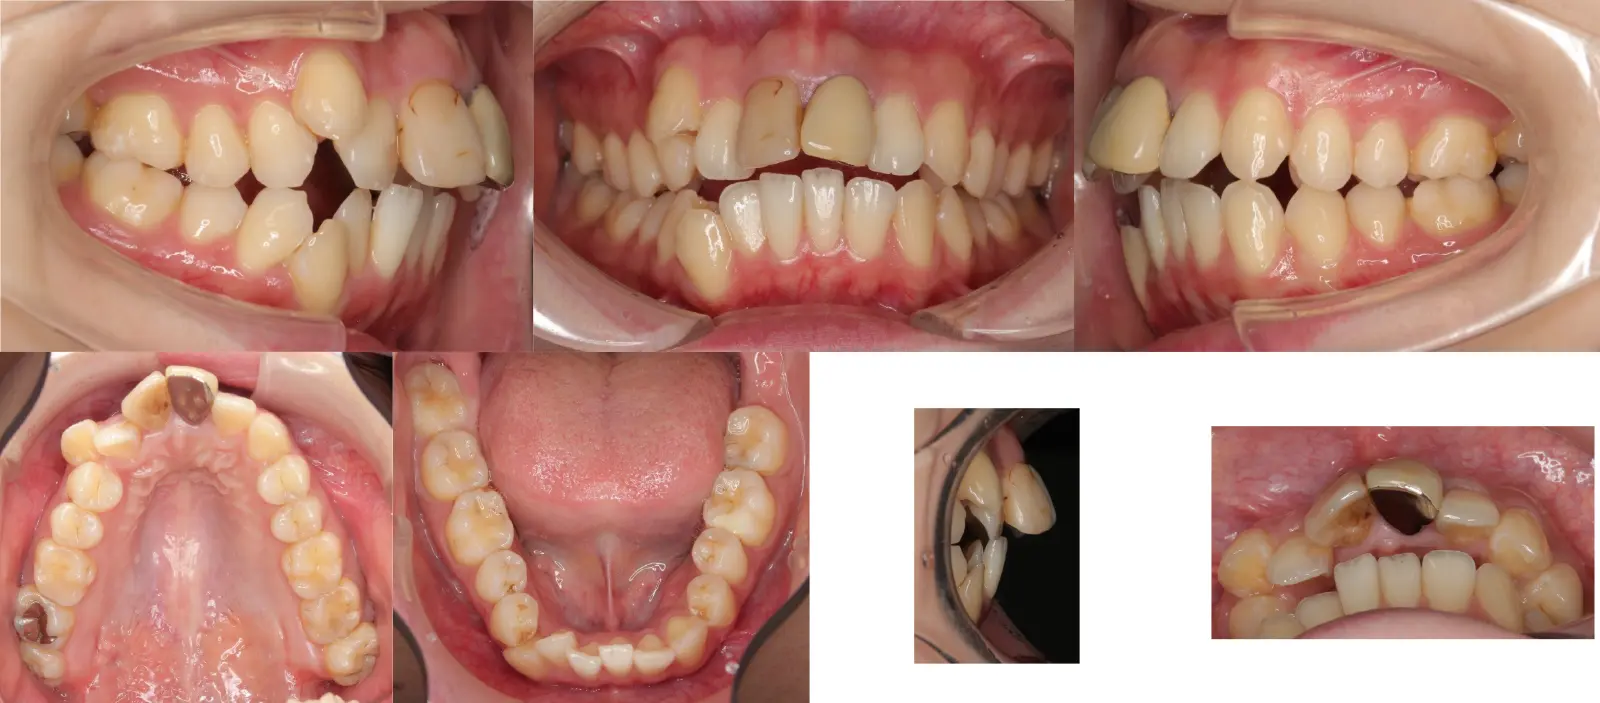

アングルⅡ級 開咬を伴う上顎前突症

- 主訴

前歯がかみ合わない

- 年齢

10代

- 治療期間

2年1ヶ月

- 治療回数

24回

- 治療に用いた主な装置

カスタムメイド型マルチブラケットタイプのデジタル矯正装置(インシグニア)

i-station(口蓋型アンカースクリュー)

- 治療費

650,000円(税別)、調整料5,000円(税別)

※伊那分院にて治療

- 抜歯部位

上顎第一小臼歯2本

下顎第二小臼歯2本